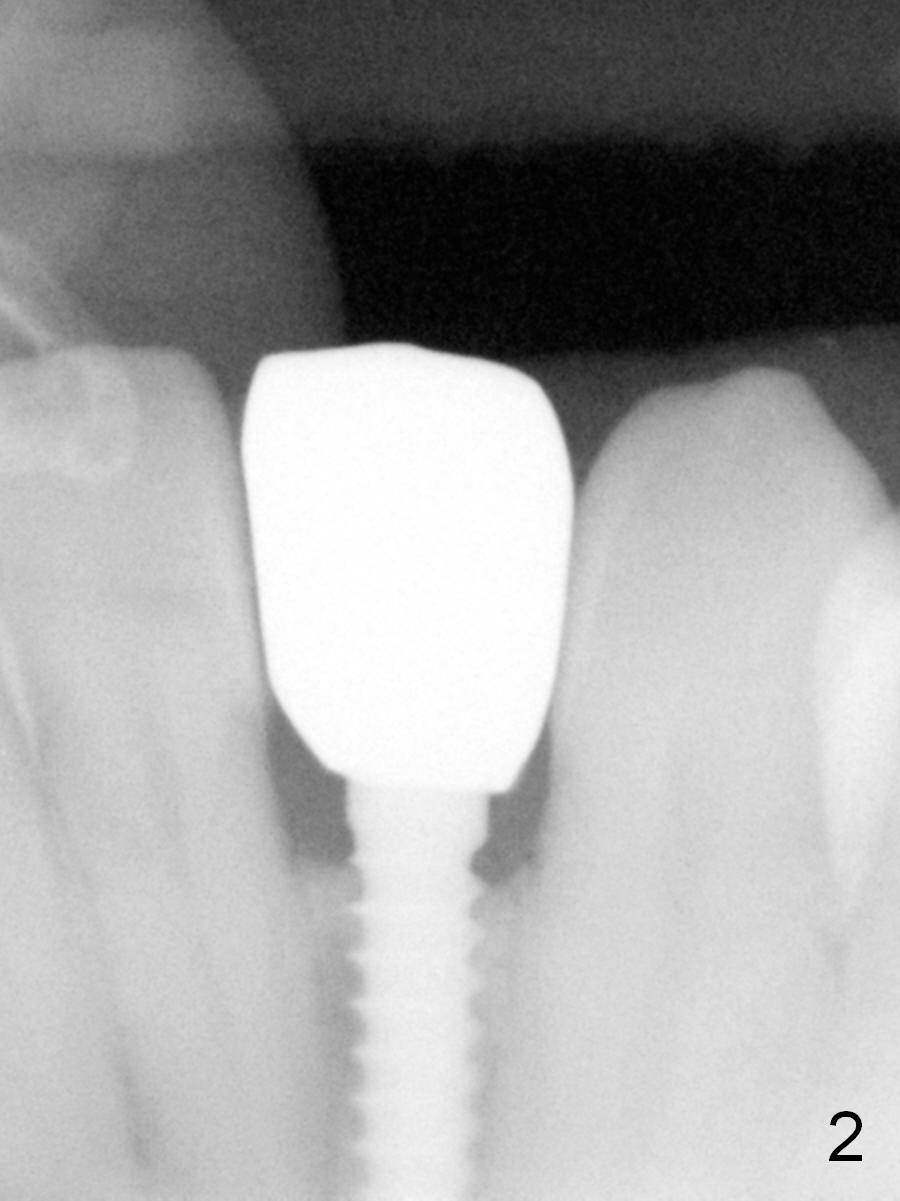

Suggestions for #23 implant crown redo (Fig.1, 2)

has been placed for 2 years 8 months.

It has already osteointegrated.

The buccal surface of the abutment has been further reduced prior to final impression (the previous cast is enclosed in the case).